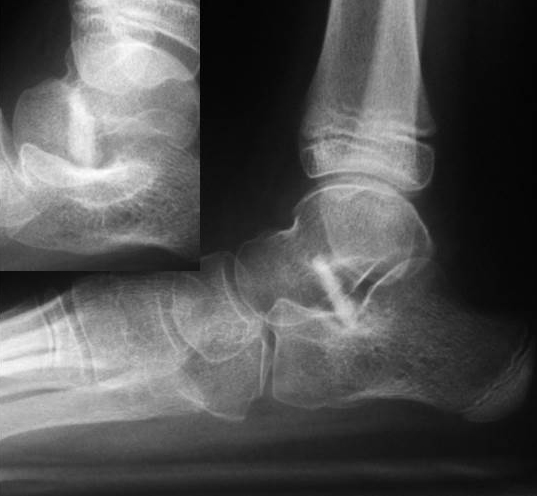

• Röntgenkontrolle (Bild 21,22).

• Im dargestellten Fall war zusätzlich eine plantarflektierende Cuneiforme mediale Osteotomie mit resorbierbarem Knochenersatz und eine Wadenmuskeldissektion nach Vulpius durchgeführt worden.

• Röntgen des dargestellten Falles 3 Monate post OP (Bild 25,26)